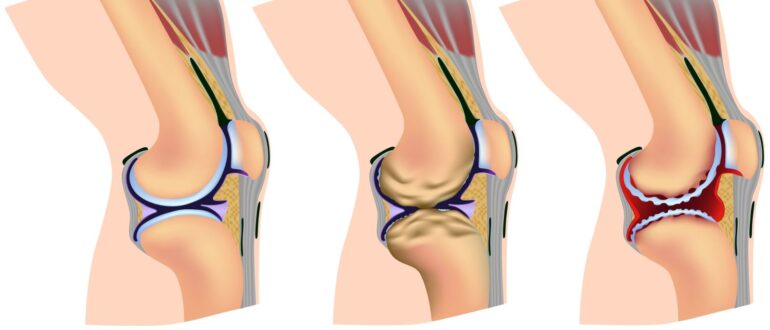

Посттравматический артрит: причины, механизм развития Причиной посттравматического артрита выступает повреждение сустава, а также околосуставных тканей — мышц, связок, сухожилий, костей, сосудов, нервов. Сам хрящ страдает достаточно редко в…